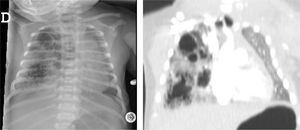

ResultadosEl estudio incluyó a 116 pacientes, 98 (84,4%) asintomáticos y 18 (15,5%) con clínica relacionada con la malformación pulmonar y manifestada antes de la cirugía. En este grupo, 10 pacientes (55,5%) presentaron sintomatología de tipo infeccioso y 8 clínica de dificultad respiratoria (2 pacientes con ventilación mecánica, 3 con soporte no invasivo tipo CPAP y 3 con oxigenoterapia). Las niñas presentaron clínica con mayor frecuencia que los varones en nuestro estudio (p=0,040) y la localización más frecuente fue en los lóbulos pulmonares inferiores (78,4%) (fig. 1). El tipo histológico más común fue el correspondiente a MCVAP (35,5%) seguido de secuestro intralobar (27,3%) y secuestro extralobar (11,8%) (fig. 2). Focalizando en los pacientes sintomáticos la distribución histológica fue la siguiente: MCVAP (9 casos), secuestro intralobar4, secuestro extralobar2, hiperinsuflación lobar congénita2 y blastoma pleuropulmonar1 (fig. 3). Considerando las variables analizadas en ambas cohortes de pacientes, sintomáticos y no sintomáticos, hemos detectado que el tamaño de la lesión en la TC fue significativamente más grande en el grupo de pacientes que desarrollaron sintomatología (p=0,027) (fig. 4). Aunque no alcanzó significación estadística, el desplazamiento mediastínico en la ecografía prenatal de los pacientes sintomáticos fue también más frecuente. Con respecto al eventual impacto de la presencia de clínica previa en el curso intra y postoperatorio, la tasa de conversión a cirugía abierta fue mayor en los pacientes sintomáticos sin repercutir de una manera significativa en la duración de la estancia hospitalaria (tabla 1). Por otra parte, no se identificaron un mayor número de complicaciones postoperatorias en el grupo de pacientes con síntomas previos (tabla 1). Los tipos de complicaciones recogidas en nuestro estudio fueron: sangrado, fuga aérea persistente, enfisema subcutáneo severo, fiebre mantenida y sepsis.

Por otra parte, hemos analizado el posible impacto de algunos hallazgos o características prenatales de la malformación en el desarrollo de sintomatología posnatal. La presencia de hidrops y/o desplazamiento mediastínico están descritos en la literatura como factores de mal pronóstico, junto con un volumen grande de la lesión detectados en la ecografía prenatal33–35. En nuestro estudio, el tamaño de la lesión determinada mediante TC posnatal fue significativamente mayor en el grupo sintomático pero el desplazamiento mediastínico, habitualmente producido por una lesión voluminosa, detectado en la ecografía prenatal no llego a alcanzar significación estadística probablemente debido a lo reducido de la muestra. Aunque la información obtenida mediante el diagnóstico por imagen es muy útil y cada vez más precisa, la correlación entre ecografía fetal y TC posnatal no pasa actualmente de ser discreta36. Hay que destacar la relativa baja incidencia de malformaciones híbridas (MCVAP+secuestro) en nuestra cohorte. Esto es probablemente debido a que lesiones inicialmente consideradas híbridas en la TC diagnóstica se convertían posteriormente en secuestro intralobar en el estudio anatomo-patológico. Un mayor conocimiento y precisión adquirido en los últimos años en las técnicas histológicas puede ser responsable de ello.